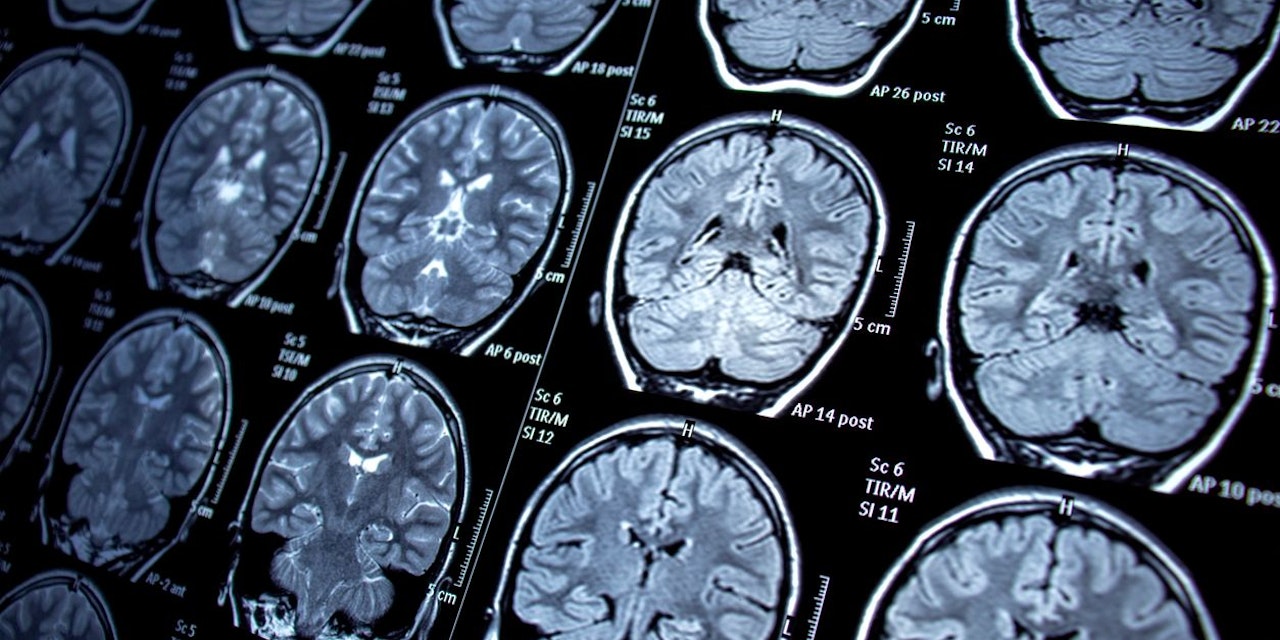

Für die Überprüfung ihrer Hypothese, untersuchten die Forscher Magnetresonanztomograph-Aufnahmen von rund 2.000 Erwachsenen zwischen 29 und 91Jahren mit und ohne akademischem Abschluss. Die Hirnalterung wurde als Hirnatrophie - also einen Verlust an Hirnvolumen - operationalisiert, die sowohl mit normalen also auch pathologische Alterungsprozessen einhergeht.